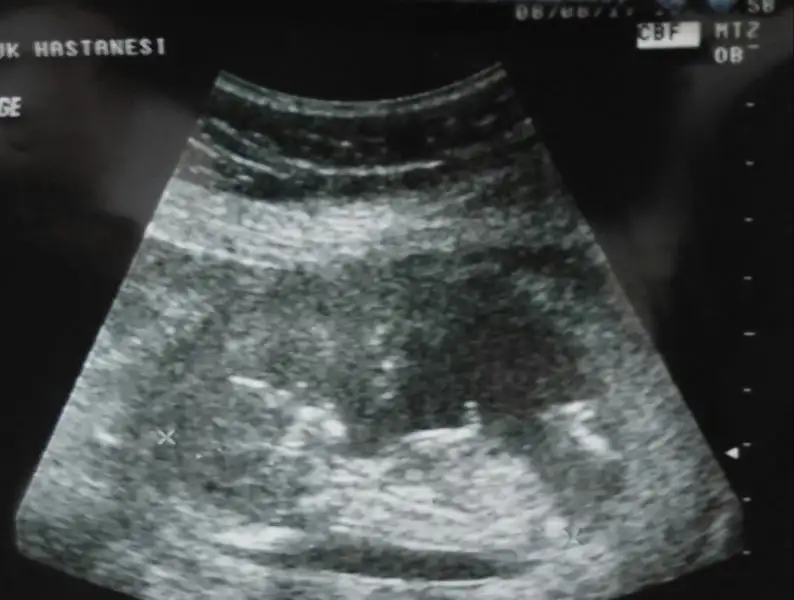

Senin ultrason resmin var mı? Bide nub icin varmıydi bak hatırlamıyorum. Bana doktor 13 ten sonra söylerim değismez dedi. Oğlumdada 14+3e kadar birsey dememişti sonrada 100de 100 demişti. Simdi yine bekliyorum ondan 14 hafta dolmasıni. Bide 4 boyutlu bakıyor ondan sanırım.

Bu bugünkü usg canim 11 haftalikken kiza benzetmistik genelde nubu. Ben artik 5 aylık olunca detayli usg ye girecem nasipse

• 20170808_223402-1.webp

17,9 KB · Görüntüleme: 62